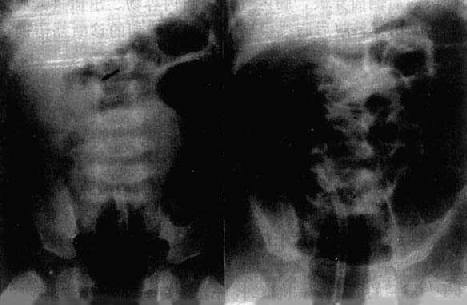

(四)空腔器官积气、积液并管腔扩大 胃肠腔内积气、积液和管腔扩大表现最常见于梗阻性病变,也见于炎症和外伤。十二指肠降段梗阻,其近侧的胃和十二指肠球部明显胀气扩大,表现出“双泡征”。小肠和结肠充气扩大,在气体衬托下,可通过观察肠粘膜皱襞的形态而将它们区分(图4-1-2)。同时也可据以分析梗阻平面,观察肠曲位置、排列形式、活动度以及肠粘膜皱襞增粗、肠壁增厚等改变。

图4-1-2 不同肠段胀气表现

空肠:肠腔内较多环状皱襞

回肠:肠腔内不见环状皱襞

结肠:可见结肠袋的间隔